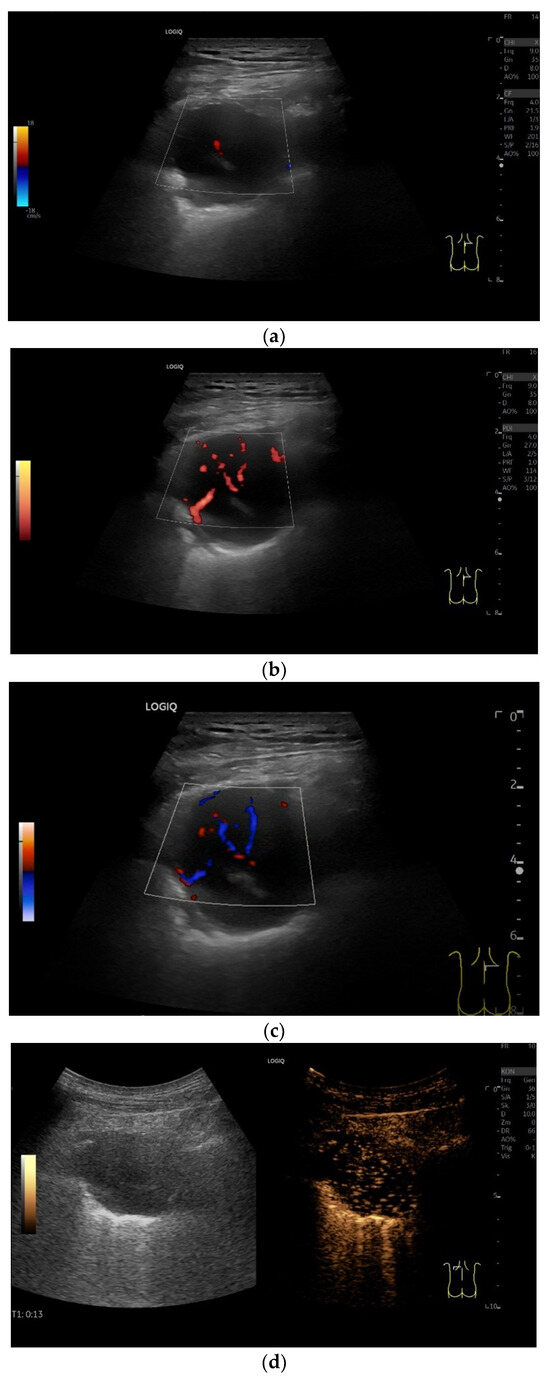

| Splenosis | Round, homogeneous lesions. Macrovessels on CDI are possible. Spleen-typical contrast behavior in CEUS with long-lasting contrast enhancement over several minutes. |

| Lipoma | Homogeneous or heterogeneous hypoechoic mass without any calcification or internal vascular supply. Slight heterogenous hypoenhancement on CEUS. |

| Benign solitary fibrous tumor | Smoothly bordered, hypoechoic. Examples with a nodular shape have been described. Larger tumors can have cystic parts. With few data and based on our example, the solid parts are hyper-enhanced in CEUS. |

| Schwannoma | Round or oval, smoothly bordered, hypoechoic. Cystic parts are typical, especially in larger tumors. In CEUS, the solid parts are hyper-enhanced. |

| Solitary extramedullary plasmacytoma | Round, hypoechoic tumor. Macrovessels on CDI. Homogeneous hyper-enhancement on CEUS. |